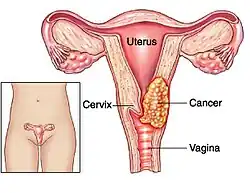

El cáncer de cérvix, carcinoma de cérvix, cáncer de cuello de útero o cáncer de cuello uterino incluye las neoplasias malignas que se desarrollan en la porción fibromuscular inferior del útero que se proyecta dentro de la vagina.

- Estadio I: confinado al cuello del útero. Con un estadio IA si el tumor mide menos de 7 mm de superficie y 5 mm de invasión en profundidad; y un estadio IB si el tumor mide más o es macroscópico.

- Estadio II: se extiende más allá del cuello, pero no se extiende a la pared de la pelvis y, si afecta a la vagina, no llega a su tercio inferior. Se clasifica como IIA si no afecta a parametrios (IIA1 si es menor de 4 cm y IIA2 si es mayor) y IIB si los afecta.

- Estadio III: el carcinoma se extiende a la pared pelviana. En la exploración al tacto rectal no existe espacio entre el tumor y la pared pelviana; el tumor se extiende además al tercio inferior de la vagina. Sería un estadio IIIA si afecta al tercio inferior de la vagina, y un IIIB si afecta pared pélvica o tiene repercusión sobre el riñón.

- Estadio IV: estadio metastásico local (puede infiltrar la pared de la vejiga urinaria o el recto) (IVA) o a distancia (IVB), por ejemplo si aparecen en los pulmones.